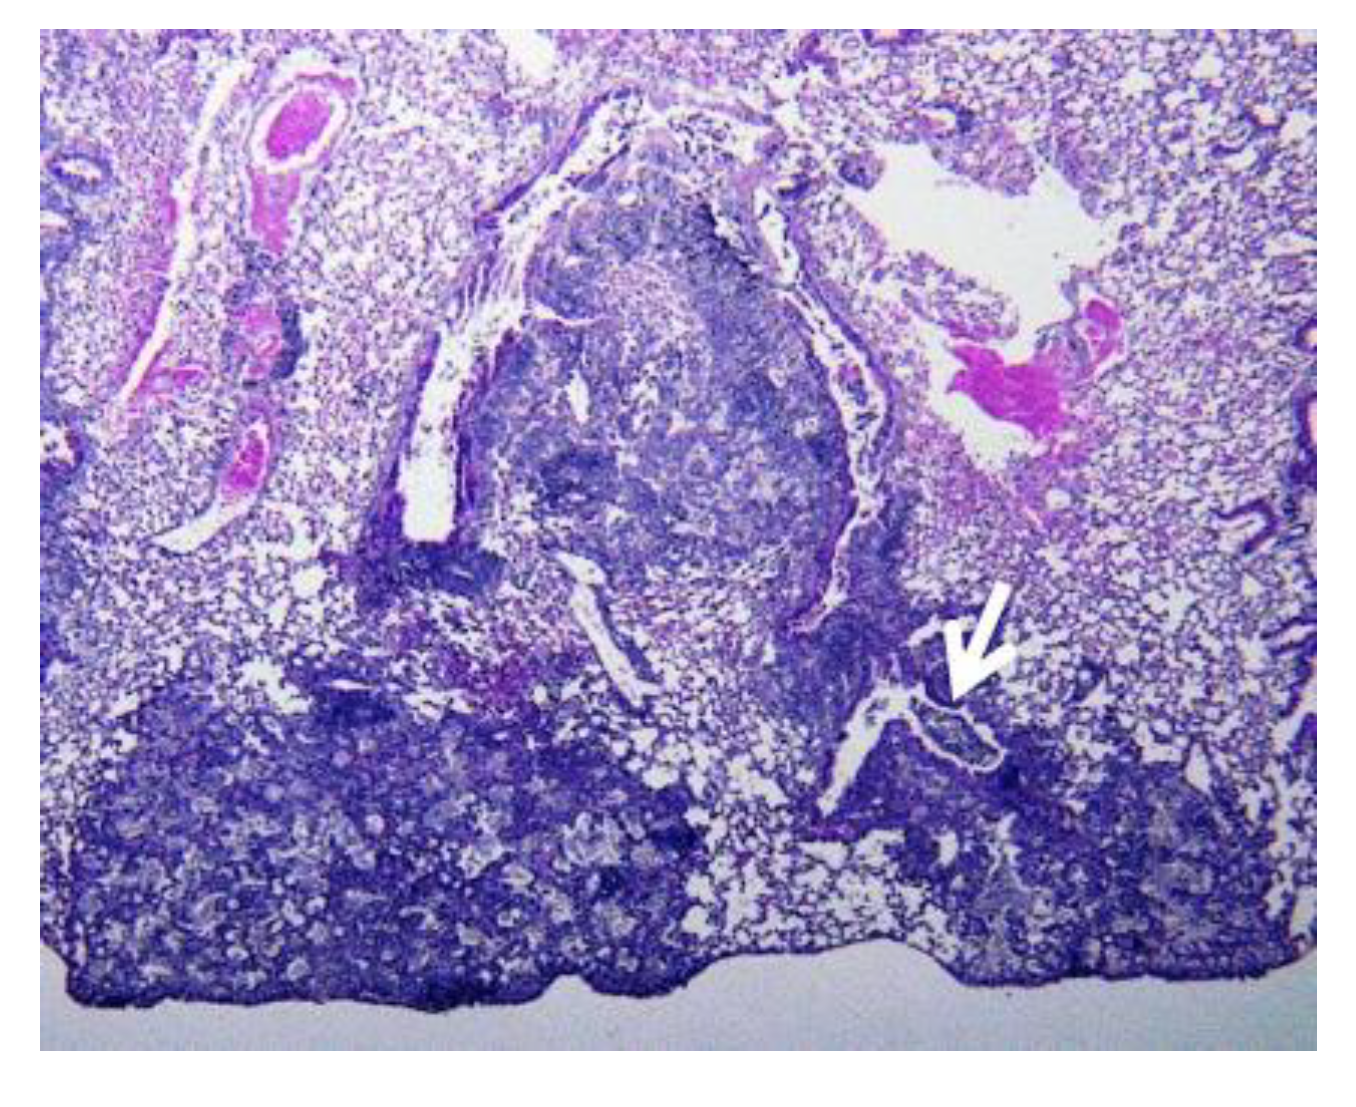

- Hunter, R.L.; Actor, J.K.; Hwang, S.-A.; Karev, V.; Jagannath, C. Pathogenesis of post primary tuberculosis: Immunity and hypersensitivity in the development of cavities. Ann. Clin. Lab. Sci. 2014, 44, 365–387. [Google Scholar]

- Hunter, R.L. Tuberculosis as a three-act play: A new paradigm for the pathogenesis of pulmonary tuberculosis. Tuberculosis 2016, 97, 8–17. [Google Scholar] [CrossRef]

- Hunter, R.L.; Olsen, M.R.; Jagannath, C.; Actor, J.K. Multiple roles of cord factor in the pathogenesis of primary, secondary, and cavitary tuberculosis, including a revised description of the pathology of secondary disease. Ann. Clin. Lab. Sci. 2006, 36, 371–386. [Google Scholar]

- Hunter, R.L.; Olsen, M.; Jagannath, C.; Actor, J.K. Trehalose 6,6′-dimycolate and lipid in the pathogenesis of caseating granulomas of tuberculosis in mice. Am. J. Pathol. 2006, 168, 1249–1261. [Google Scholar] [CrossRef]